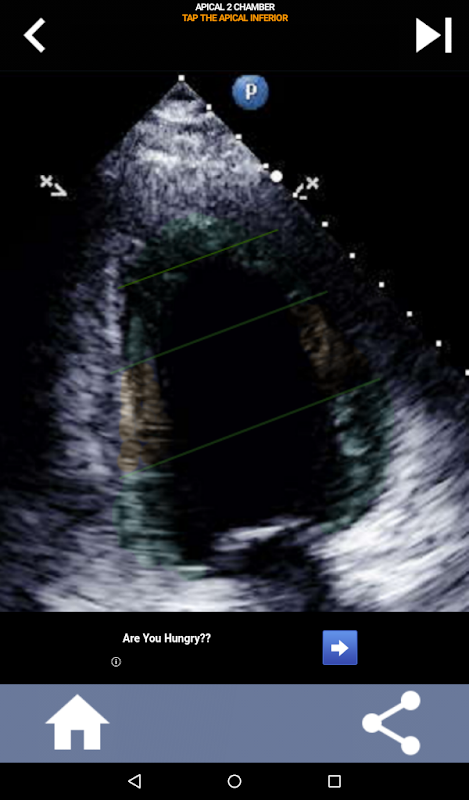

이 응용 프로그램은 AHA로 구분 된 심근을 보여주는 모든 반향보기를 포함하고 올바른 부분을 탭하도록 퀴즈 것입니다. 나는 개인적으로 빨리 반복적 인 퀴즈가 나를 위해 가장 잘 작동한다는 것을 알았다. 나는 주제를 빨리 배우고 암기해야한다. 당신이 에코 / TTE를 공부하는 초음파 학생이라면, 이것은 당신의 연구에 훌륭한 보완책이 될 것이라고 생각합니다.